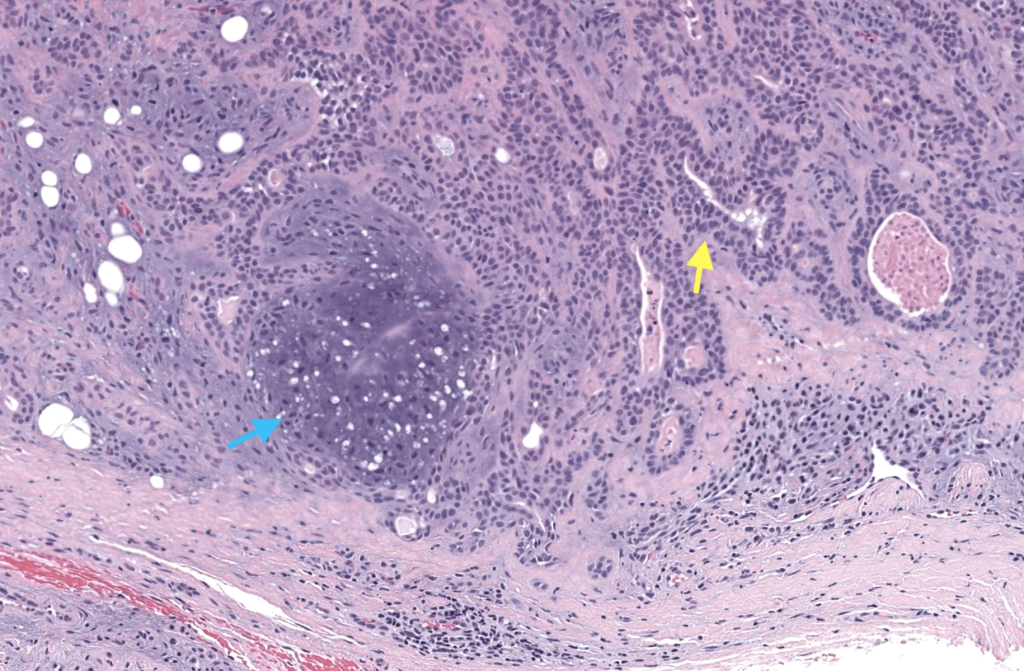

- Nombres: Tumor mixto cutáneo, Siringoma condroide, Adenoma pleomórfico de la piel (por su similitud histológica con el adenoma pleomorfo de glándulas salivales) Obaidat 2007,Wan 2018

- Historia: Probablemente descrito por Nasse en 1892 como tumor mixto de piel. El término “Siringoma condroide” fue propuesto por Hirsch y Helwig en 1961 en una serie clásica de casos.Kallam 2013 (citando Hirsch & Helwig)